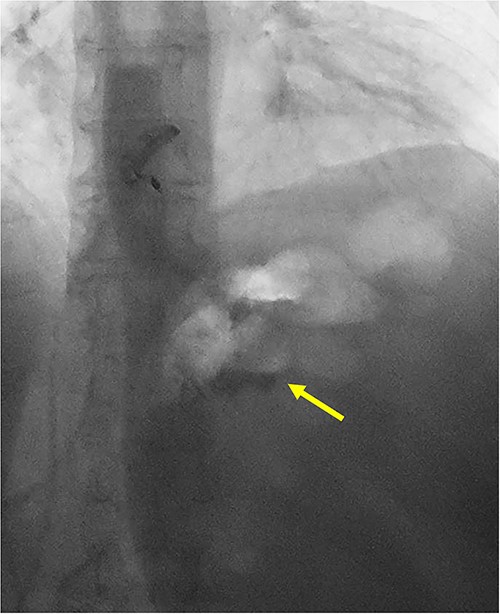

She underwent a CT of her abdomen and pelvis that showed concern for a possible gastrogastric fistula (Fig. 1) that was confirmed via an upper GI series demonstrating the passage of oral contrast into the remnant stomach (Fig. 2). Subsequent esophagogastroduodenoscopy (EGD) also revealed an ulcer at the site of the GGF (Fig. 3). The patient was discharged home on Omeprazole twice daily. She was seen in the outpatient setting with bariatric surgery and scheduled in 3 months for laparoscopic take-down of her gastrogastric fistula.

Pre-operative EGD demonstrating wide-mouthed gastrogastric fistula with an associated ulcer.

An intra-operative EGD was performed to assist with localizing the GGF and demonstrated a wide-mouthed fistula ~2 cm proximal to a widely patent GJ without an associated marginal ulcer. Purple cartridges on the Signia staple gun were then used to divide the remnant stomach at the level of the mid-body as well as the lateral aspect of the gastric pouch. Extreme care was taken to ensure the GJ and roux limb were preserved and not injured during this step. The en-bloc GGF specimen was removed and inspected on the back table demonstrating the fistulous connection between the remnant stomach and gastric pouch, ensuring a complete resection of the fistula (Figs 4 and 5). The total operative time was 1 h and 21 min.